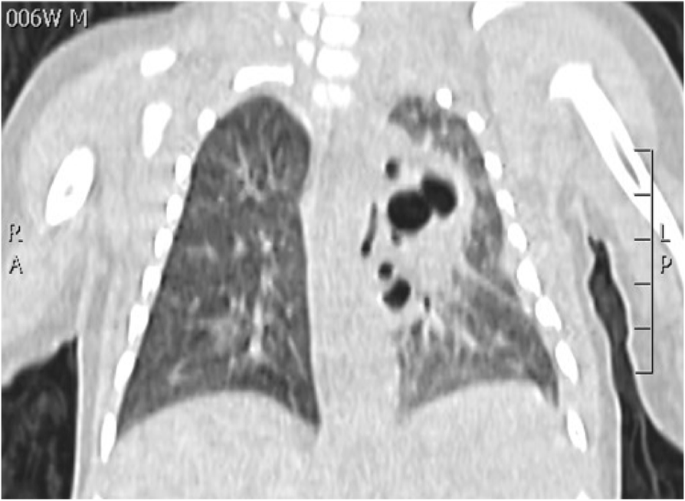

N.F. was born at 37+3 weeks g.a. by caesarean section due to IUGR, severe polyhydramnios and breech presentation, by consanguineous parents of sub-Saharan origin. During pregnancy invasive prenatal diagnosis was performed with Karyotype and CGH Array analysis, both normal. At birth the weight was 2380 g (8°p.le), the length 47,5 cm (34 p.le), CC 33,6 cm (56° p.le). In the first hours she developed progressive respiratory distress and was transferred to NICU where was assisted with n-CPAP for 22 days (FiO2 max 0,3), followed by HFNC for other 15 days. Chest X-Rays showed lungs hypoexpansion and dysmorphic ribs with increased radiotransparency, compatible with prenatal ribs fractures (see Fig.1, rib cage deformities). Little thoracic expansion was also clinically evident. Imaging was completed with long bone x-rays that showed fractures in proximal and distal right femoral epiphysis and distal left femoral epiphysis. No vertebral fractures neither cranial fractures were detected. Echocardiography was normal as well as cerebral and abdomen ultrasound scan. Considering this clinical presentation osteogenesis imperfecta was suspected and genetic analysis by NGS was performed. However, no abnormal variants in the analysed genes were detected. LEPRE gene analysis is still ongoing. Calcium and phosphate blood levels were normal, as well as PTH, with little elevation of alkaline phosphatase. Accordingly with Reference Centre, the baby underwent two course of bisphosphonate therapy (neridronate) and began cholecalciferol therapy at initial dosage of 1000 UI per day, reduced to 500 UI after elevation of 25OHvitaminD. The negativity of genetic analysis and the hormonal assays suggest that the clinical presentation of the baby could be due to severe prenatal maternal vitamin D deficiency. Mother blood 25OHvitamin D was low and was therefore supplemented. However, phenotypical features and suboptimal growth in the following months could be due to another genetic condition that has to be investigated.